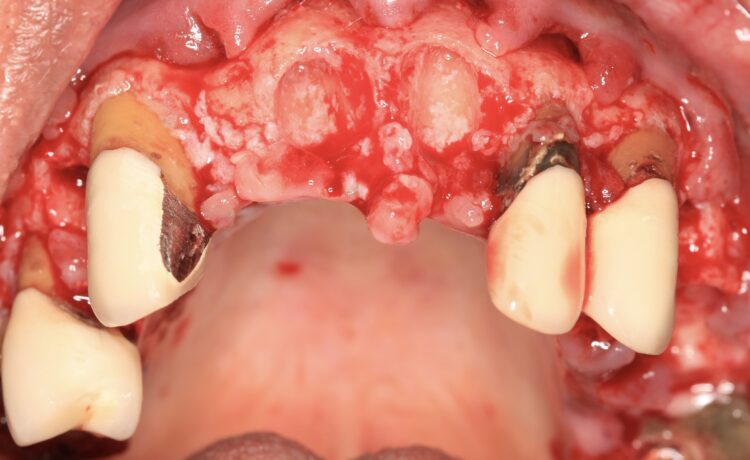

A 60-year-old male patient presented with major concerns about unsatisfactory smile appearance, limited masticatory function and pain while chewing. The patient was in good general health. The clinical and radiographic examination revealed failing ceramic restorations, rampant caries, non-restorable teeth, soft tissue inflammation, residual roots and missing teeth. Comprehensive digital records, including extraoral and intraoral clinical photographs, were collected as part of the initial assessment. The case was deemed suitable for full arch implant-retained restoration using advanced techniques.

The plan was followed meticulously on the day of surgery. The canines, left and right premolars and a right molar were used to support the surgical guide together with three bone anchor pins. Following the digital plan, all other teeth were extracted and thorough degranulation of the sockets was performed. No bone reduction was performed for both the provisional and final prosthesis in accordance with the Misch classification for an FP1 approach.[iv]

The implant beds were then prepared with the surgical guide in situ. Six CONELOG® Progressive-Line implants from BioHorizons Camlog were placed in accordance with the predetermined positions, depths and angulations. These implants were selected for this case because they feature an optimal thread design and tapered figure, promoting high primary stability – which is essential in full arch reconstruction cases.

The implants were placed through the guide for better accuracy and precision. A surgical primary stability of >35Ncm was achieved for each implant. Once the implants were placed, the surgical guide was removed, and the extraction of the remaining teeth was completed.